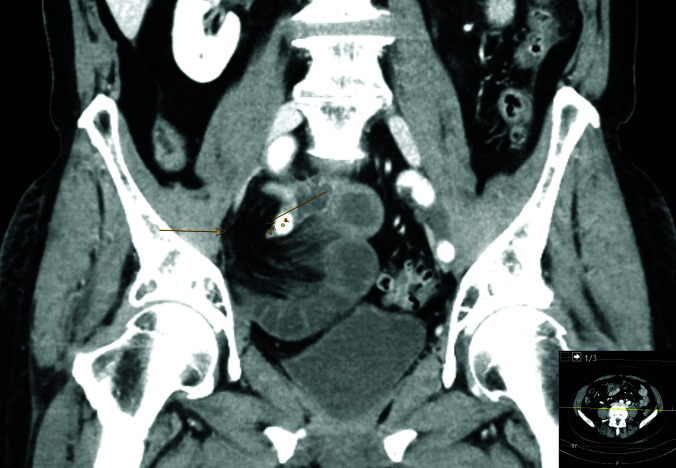

Presentation of the case: We report a case of 74-year-old male patient who presented with diffuse abdominal pain. He had undergone robot-assisted laparoscopic prostatectomy 4 months earlier. Computed tomography showed signs of internal herniation under the right external iliac vessels. The patient was operated laparoscopically with small bowel resection and peritoneal flap.